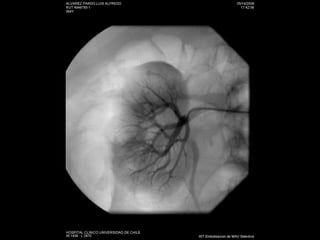

Angiografía

Embolización de lesionespostraumáticas vasculares renales.